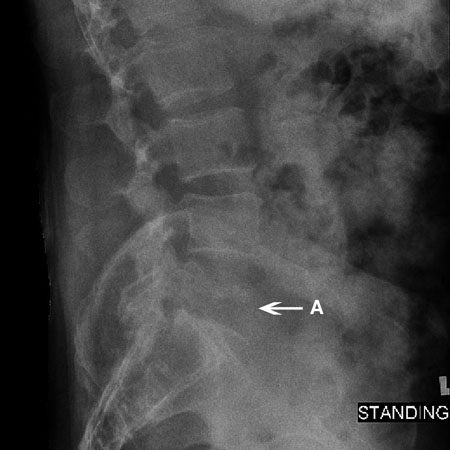

Radiograph of a compression fracture: a lateral radiograph of an L2 compression fracture (A). Wedging of the vertebral body is seen

Courtesy of Dr K. Singh; used with permission